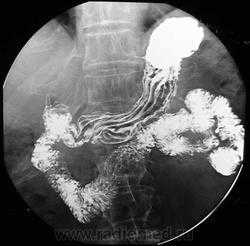

в — нижняя треть пищевода; г — сагиттальная реконструкция Картина нормального пищевода при рентгенологическом исследовании при тугом наполнении и двойном контрастировании:

а — в норме пищевод при тугом наполнении имеет диаметр около 2 см, четкие и ровные контуры;

б — после прохождения контрастной массы выявляются продольные непрерывные складки слизистой оболочки (до 4)